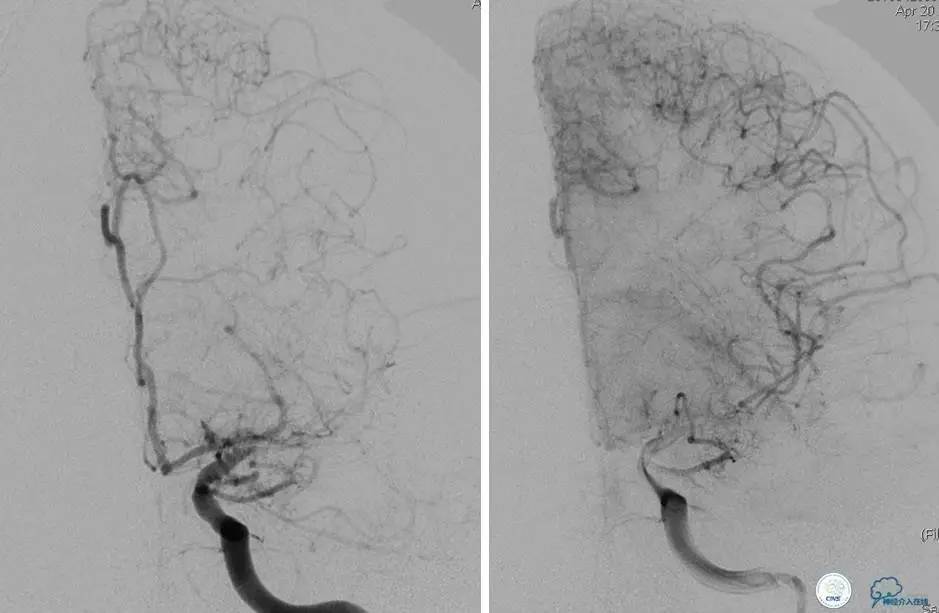

▼DSA示右侧椎动脉发育低下,弥漫性狭窄,可以看到左侧椎动脉反流,因此判断左侧椎动脉V4段CTO。

微导丝穿过闭塞段,微导管造影,球扩闭塞段,置入Wingspan支架,血流完全恢复正常。

患者术后2天再次出现卒中发作,药物治疗好转,此后病情稳定。半年后复查DSA,见支架闭塞,侧支循环开放。患者一般情况好,mRS:1分。